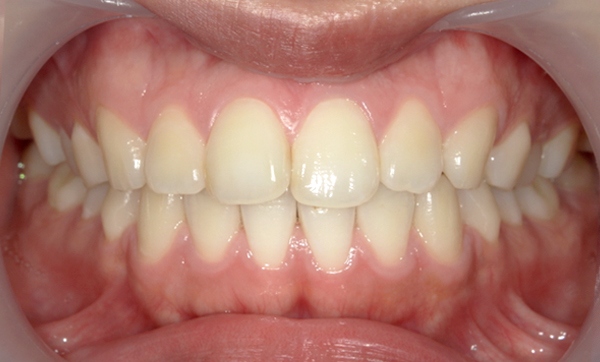

症例_001 前歯「捻転歯」症例

治療期間:6ヶ月金額:48万円+税20代女性少しのねじれ捻転歯下の八重歯

| Before | After |